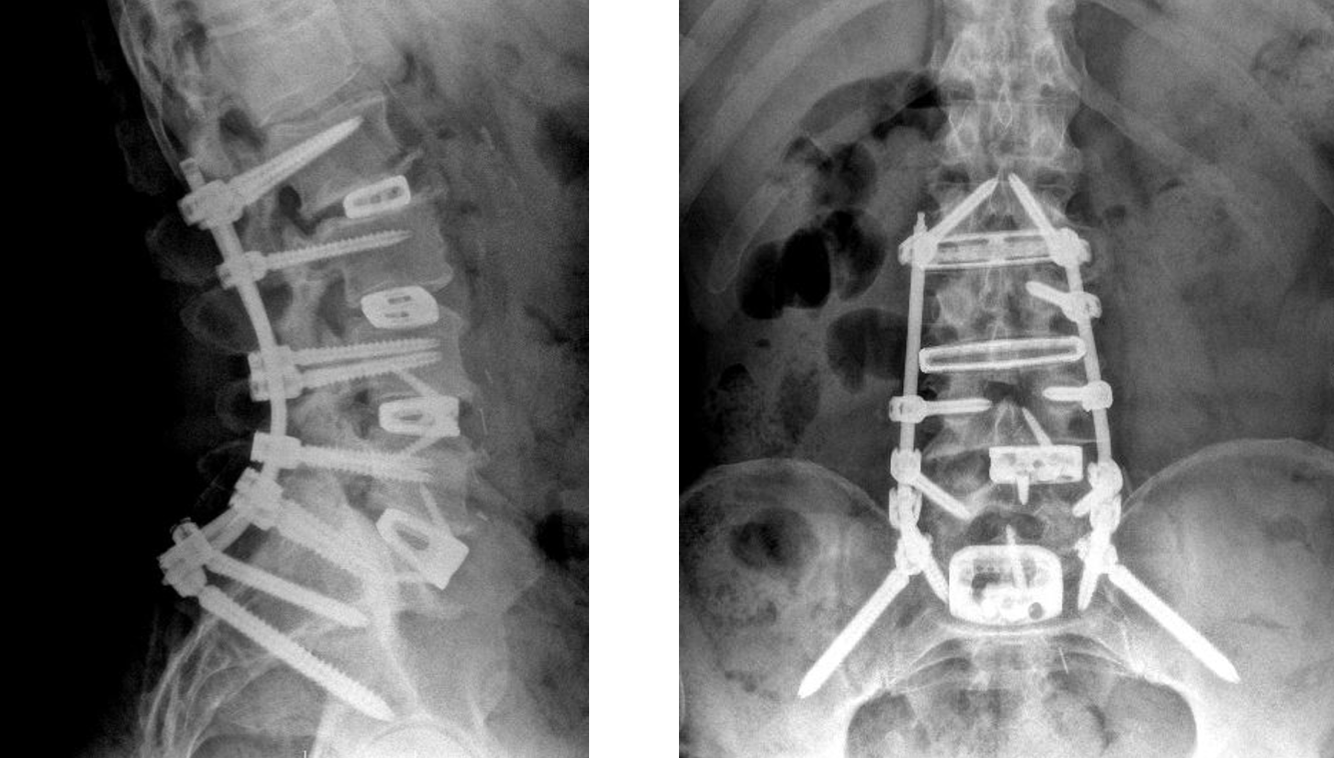

Final Result:

- Removing the degenerated disc material and placing the ALIF and XLIF cages and screws and rods can achieve the following goals:

- Improves the height and proper alignment of the collapsed disc spaces, correcting spinal deformity (scoliosis) and spinal instability (spondylolisthesis)

- Allows for removal of pressure on the nerves, relieving radiating leg pain

- Provides biomechanical stability to the bones as they are fusing, reducing the incidence of screw loosening

- Increases the chances that the fusion will heal successfully

Before:

After:

Scoliosis Correction:

- In some cases as the lumbar discs degenerate they collapse more on one side creating angular deformity and scoliosis (curvature of the spine).

- Placing the cages creates a parallel space between the bones, correcting the scoliosis.

- Further correction of the scoliosis is achieved with the screws and rods.

- In some cases the fusion will be taken up to the T10 level with the screws and rods.